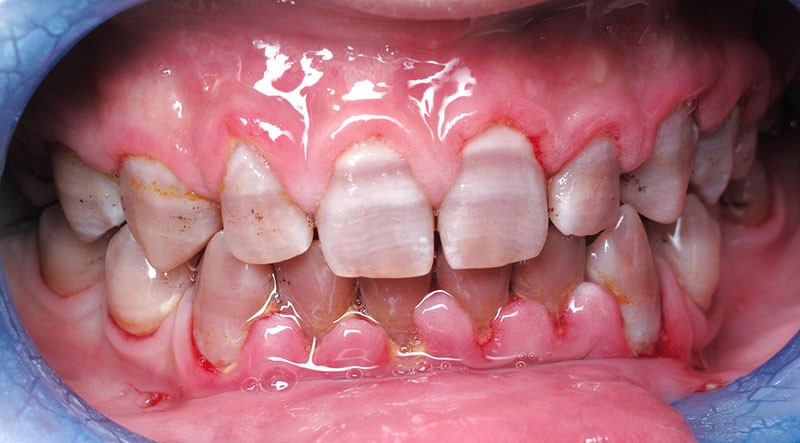

Teinte opalescente grise à jaune ambrée, couronnes globuleuses, calcifications intra-pulpaires, racines fines et courtes, attrition précoce, nécrose aseptique… Ces anomalies cliniques et radiographiques décrivent le tableau de la dentinogenèse imparfaite (DI) isolée de type 2. Cette anomalie génétique à transmission autosomique dominante est liée à un défaut de DSPP, gène de la sialophosphoprotéine dentinaire [1, 2]. Des anomalies dentinaires similaires résultent également de mutations de ce gène. Les avancées en recherche génétique tendent à réunir ces pathologies sous une même étiologie.

Un diagnostic précoce est primordial, car il existe aussi une forme associée à une anomalie osseuse, l’ostéogenèse imparfaite. Le chirurgien-dentiste est donc au premier plan pour dépister ces anomalies et limiter dès le plus jeune âge leurs conséquences infectieuses, fonctionnelles et esthétiques.